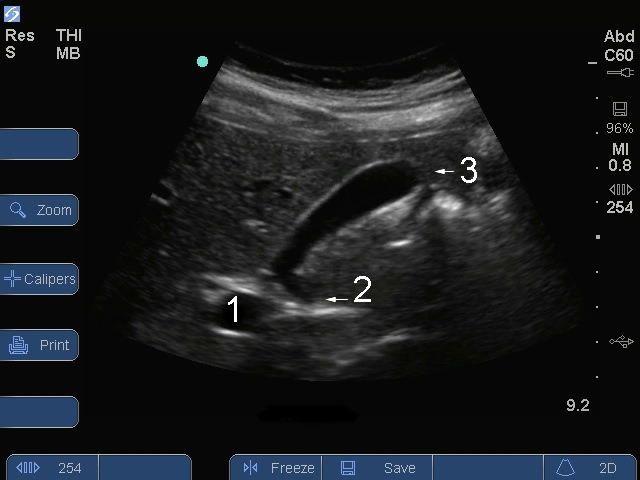

胆嚢頚部縦断面画像

S シリーズ: 胆嚢頚部縦断面

門脈 (PV)

頸部

底部